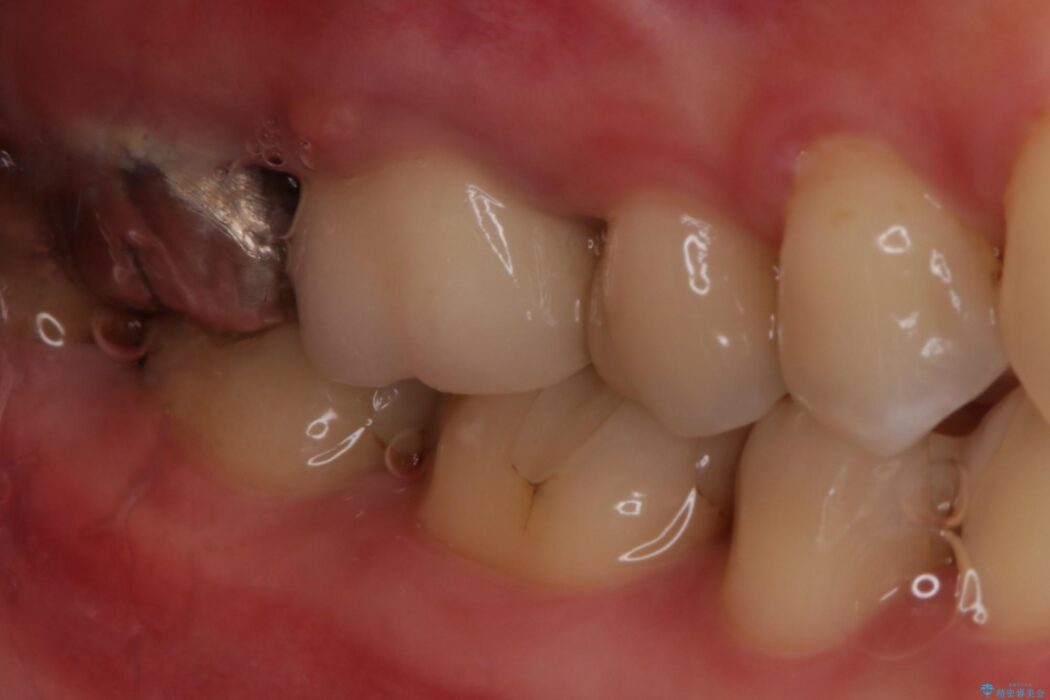

別の部位の治療で通われていた患者様ですが、歯ぐきにできものが繰り返しできるとのことで相談されました。

X線画像を診断すると、充填不良の根管の先に透過像が認められたため、再根管治療をご提案いたしました。

根管治療を再度行うことでフィステル(ニキビのようなできもの)は消失しました。

最終的にセラミッククラウンによる補綴治療を行いました。